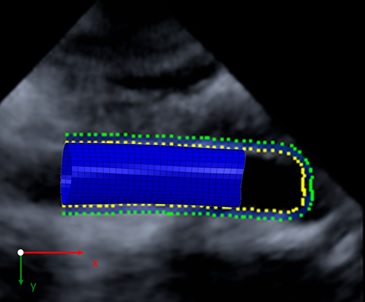

Patient individual Finite Element Analysis of the human aorta based on real time 3D ultrasound measurements combined with speckle tracking

Copy of Figure 3